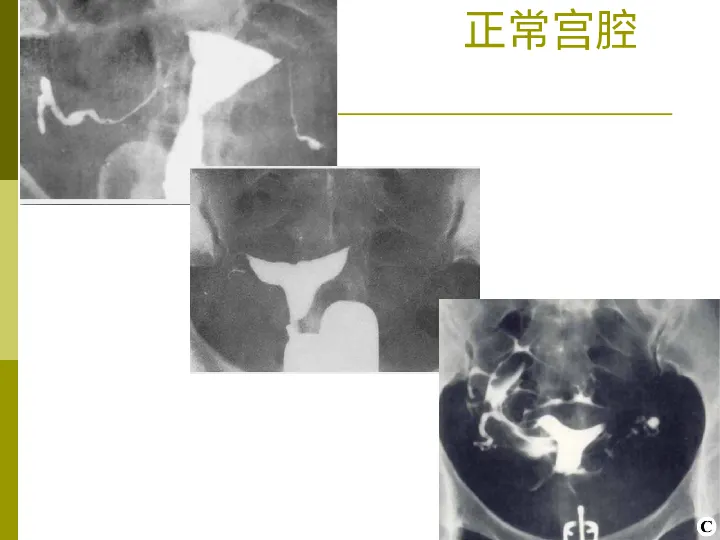

>【影像PPT】子宫输卵管造影术

【影像PPT】子宫输卵管造影术